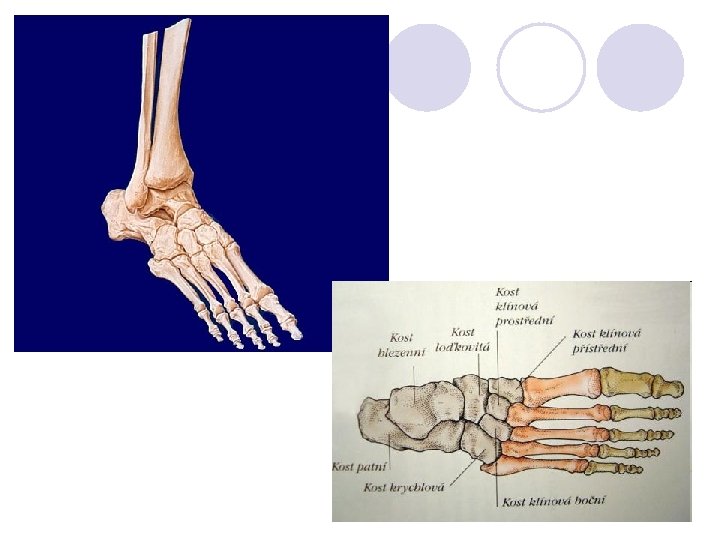

Kostra dolní končetiny – OSSA MEMBRI INFERIORIS l l l Noha – PES Kosti zánártní – OSSA TARSI Kost hlezenní – TALUS Kost patní – CALCANEUS Kost krychlová – OS CUBOIDEUM Kost loďkovitá – OS NAVICULARE Tři kosti klínové – OSSA CUNEIFORMIA Kosti nártní – OSSA METATARSI Kost nártní – OS METATARSALE 1. – 5. Články prstů – OSSA DIGITORUM PEDIS Kratší a plošší než na ruce Palec má opět jen dva články, ostatní prsty po třech